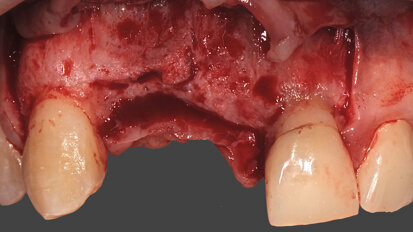

Socket preservation con acido ialuronico reticolato e riabilitazione impianto supportata di un secondo premolare superiore

La paziente si presenta in visita lamentando mobilità e l’insorgenza di un dolore alla masticazione a carico dell’elemento 25. Clinicamente ...